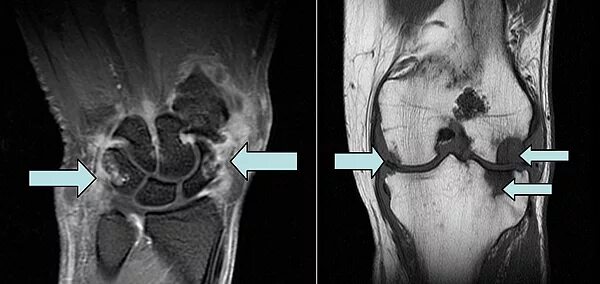

Мрт при боли в суставах